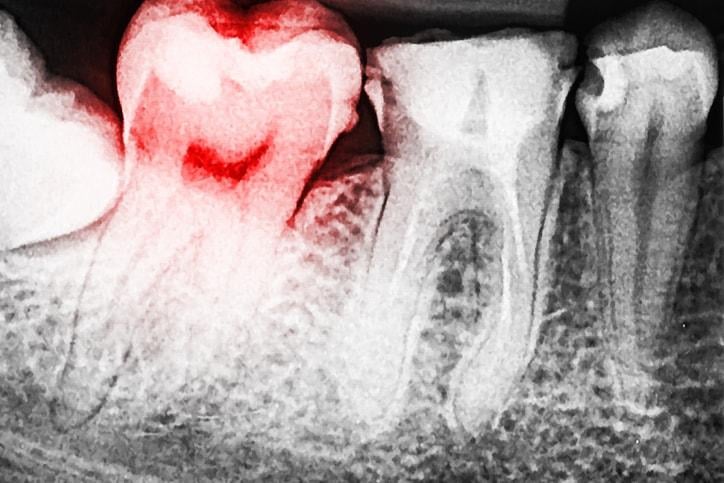

Viêm xương ổ răng là một biến chứng gây đau có thể xảy ra sau khi nhổ răng.

Sau khi bạn nhổ răng, ngay vị trí ấy sẽ hình thành cục máu đông để bảo vệ các xương cơ, các mô và dây thần kinh. Trong trường hợp bạn bị viêm xương ổ răng, cục máu đông sẽ không thể hình thành. Điều này có thể dẫn đến nhiễm trùng và khiến bạn có cảm giác đau liên tục trong 5 hoặc 6 ngày.

Khi bị viêm xương ổ răng, bạn có thể nhìn thấy nơi răng bị nhổ có mẩu xương trắng, thay vì là máu đen như bình thường. Bạn sẽ cảm thấy đau sau khoảng 2 ngày kể từ khi nhổ răng và cơn đau càng ngày càng nghiêm trọng. Tệ hơn nữa là bạn có cảm giác đau tai, hôi miệng và giảm vị giác.